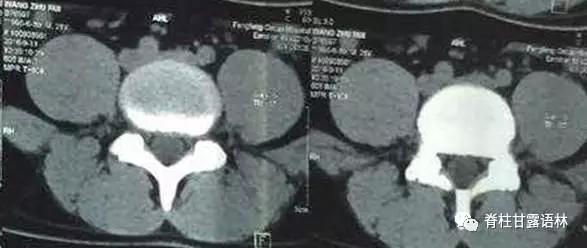

- 正常人群自身结构之多样性,如双眼皮、身高、体重、体型,客观存在;椎管之宽度、深度,髂骨之高度,亦有先天之差异;椎旁肌肉,亦复如是(图8-图11)

图8 一例年轻、男患者之腰4/5轴位CT 椎管左右径与前后径均较宽椎旁肌肉致密脂肪少关节突无增生

图9 另一例年轻、男患者之腰4/5轴位CT 椎管左右径与前后径均较小 椎旁肌肉致密脂肪少关节突无增生